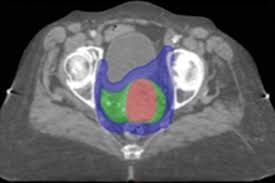

A External Beam Radiation Therapy 3dcrt Planning For Endometrial Download Scientific Diagram